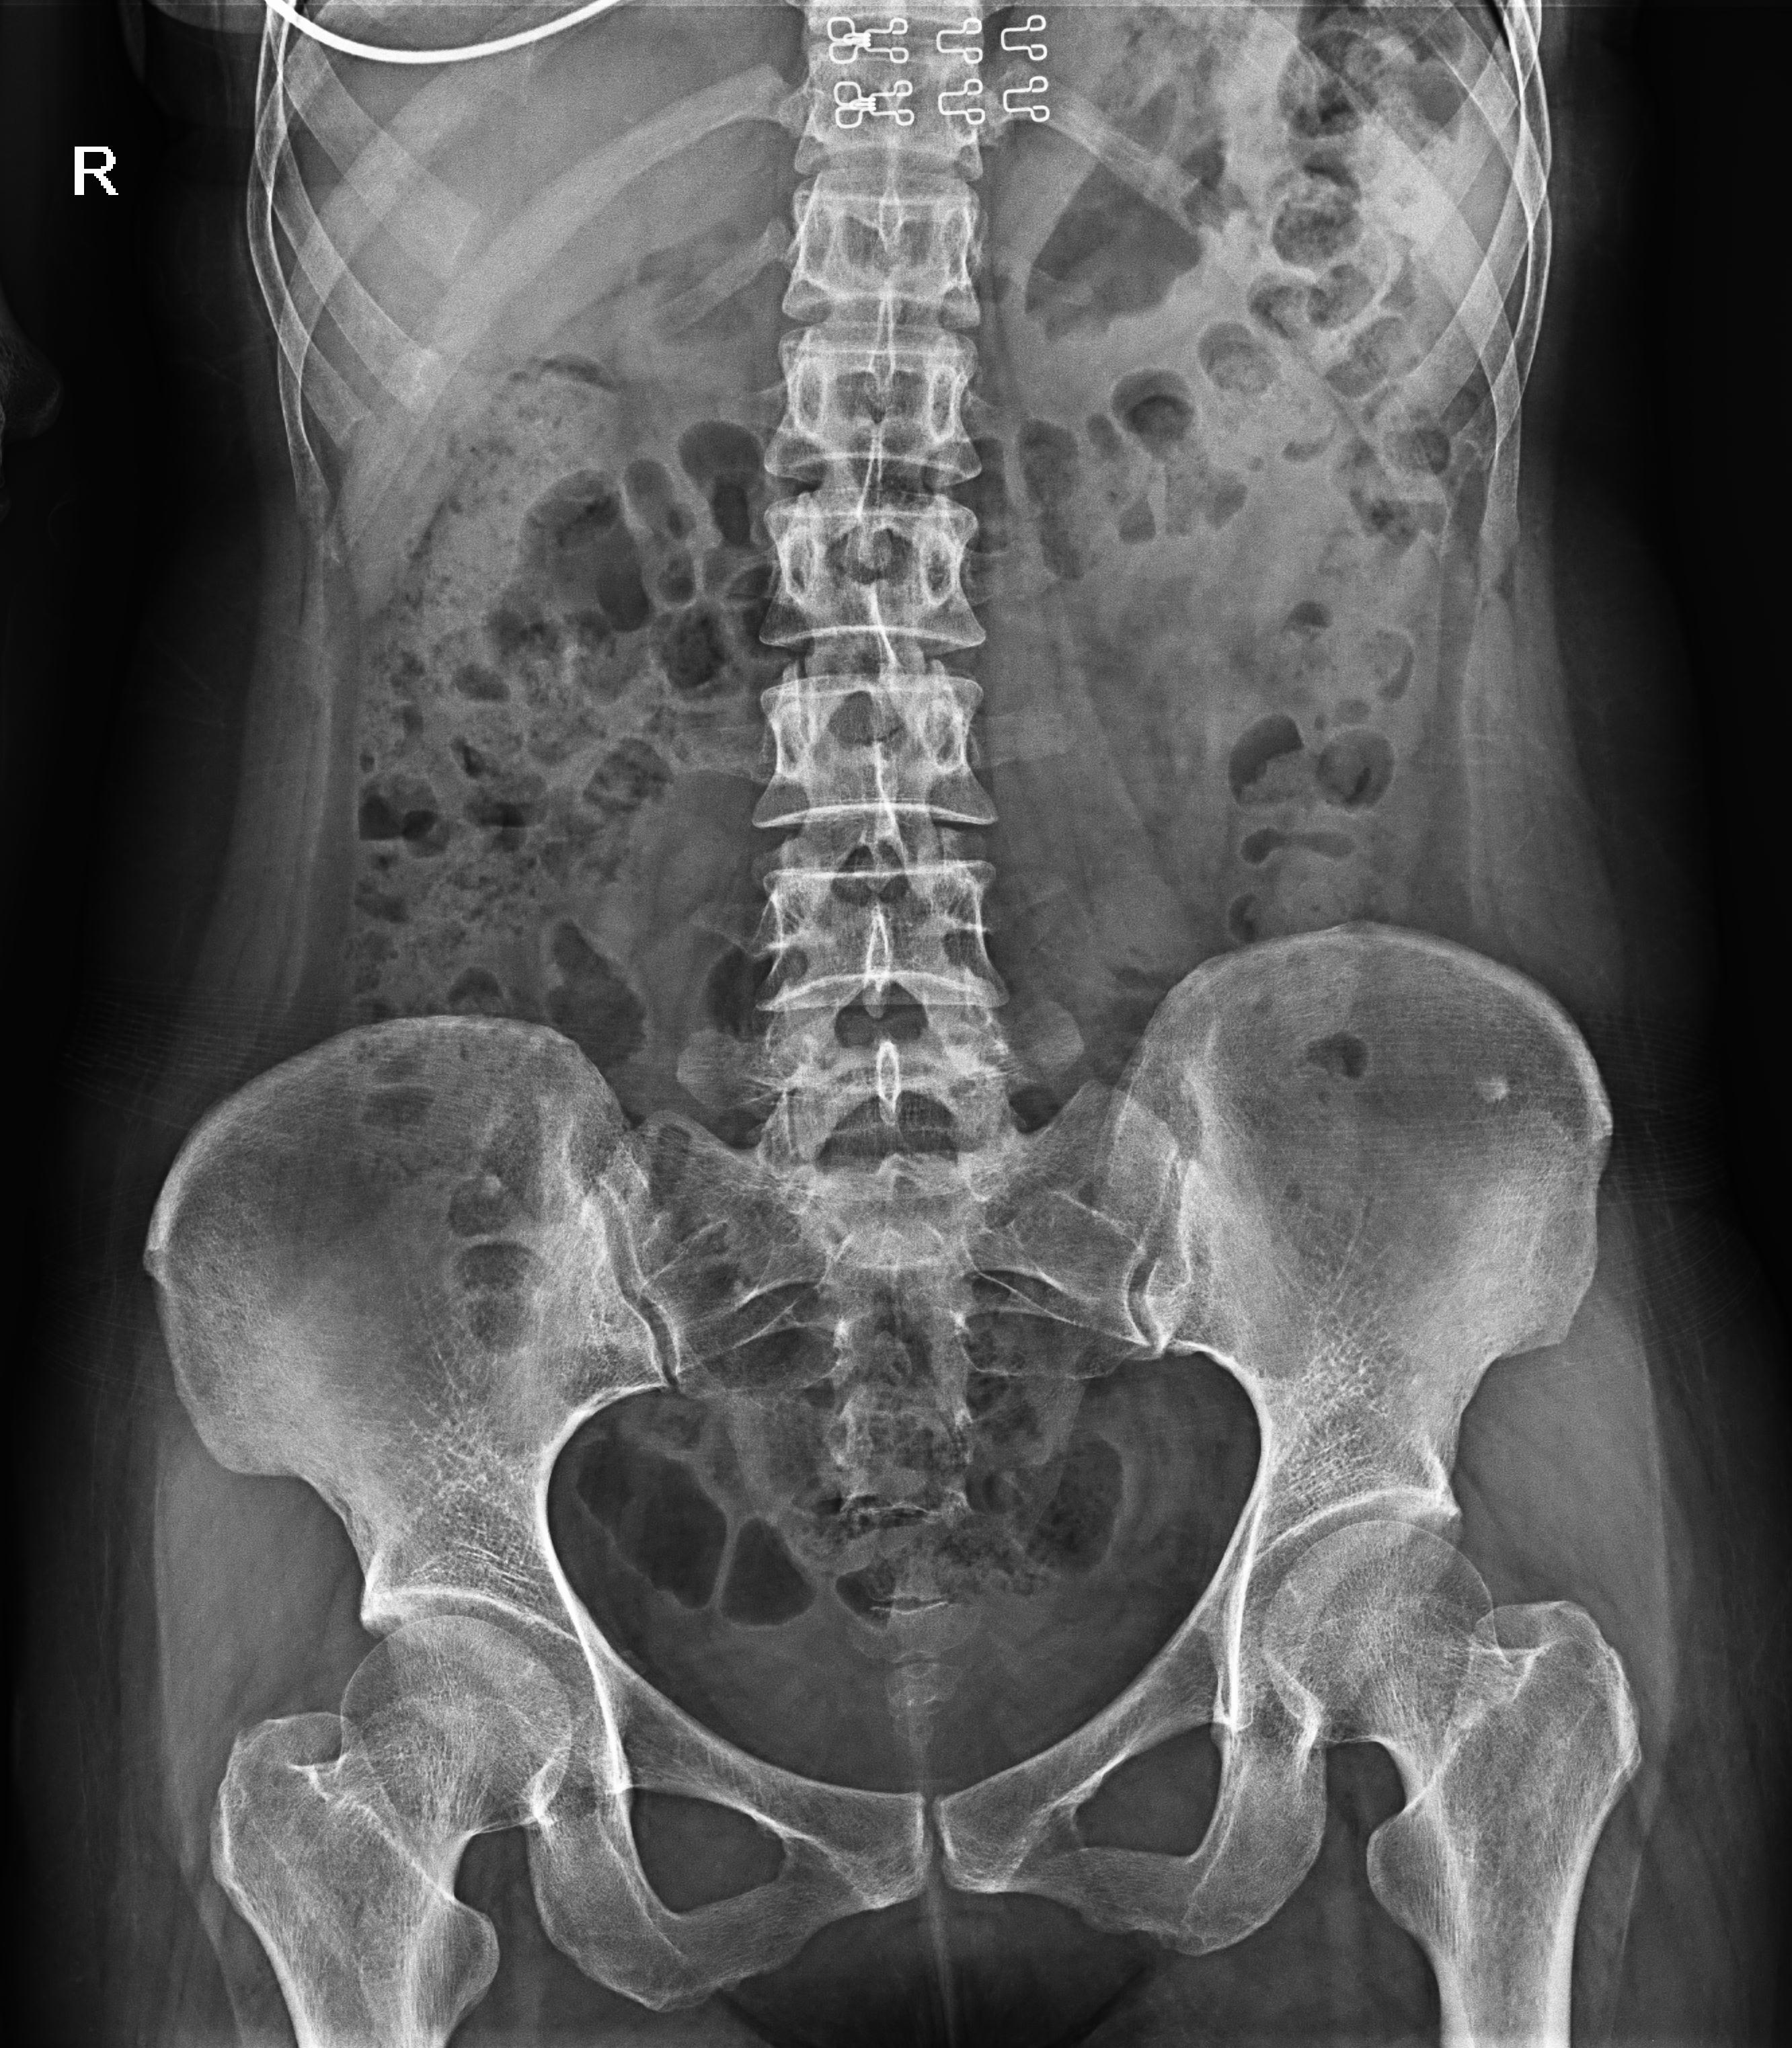

● 在可視過程或回放過程中,如發(fā)現(xiàn)疑似病灶,可進行毫秒級高清點片,隨時抓取單幀圖像,精準捕抓病灶。

● 獨特實用的床面升降功能,有利于DR攝影及行動不便的患者上下床;

● 床面可降至與病床平行高度,既方便醫(yī)護人員平移患者,又避免對患者的二次傷害;

● 對于醫(yī)生的近臺操作也更方便,不同身高的醫(yī)生可根據(jù)需要調節(jié)床體高度,更利于醫(yī)生開展相關近臺手術。